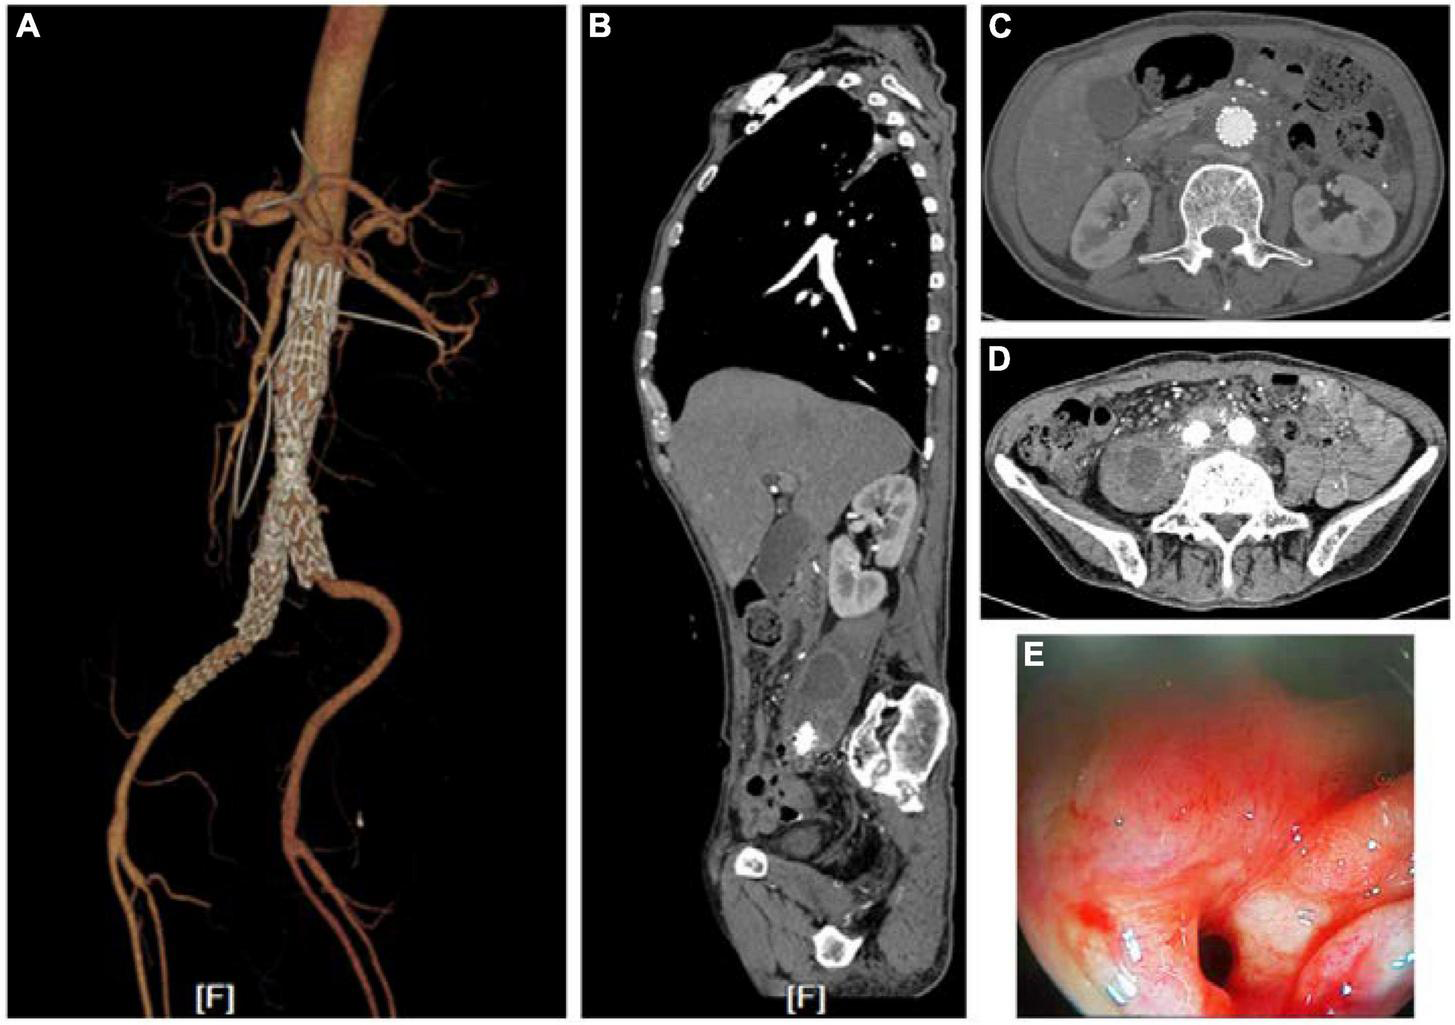

A 71-year-old man underwent two rounds of endovascular repair treatment for rupture of an aneurysm of the right iliac artery 6 months prior to the index operation. He presented with recurrent hematemesis, melena, and intermittent fever. He was treated with antibiotics according to the findings of the bacteriology examination of blood samples. PET-CT suggested a gastrointestinal stromal tumor surrounding the abdomen. Emergency endoscopy revealed a fistula of duodenum and minor hemorrhage. The fistula was found in the horizontal part of duodenum. Computed tomography angiography (CTA) scan had revealed an infected abdominal aortic aneurysm (iAAA) with low-density image surrounding the AAA and the right iliac artery (Figure 1). However, there was no evidence of contrast leakage into the intestinal tract. Blood tests at the time of the patient’s arrival revealed severe anemia, renal dysfunction, elevated white blood cell count, and high levels of serum procalcitonin and C-reaction protein. Blood culture found Escherichia coli, which was sensitive to vancomycin. Based on these findings, aorto-duodenal fistula (ADF) and iAAA were suspected.

Figure 1. Images of CTA and endoscopy before treatments. (A) Endovascular repair and drainage had been performed when the patient was hospitalized. (B–D) A low-density shadow hinting at an abscess in the right psoas major muscle and around the stenting. (E) Fistulae in the horizontal part of duodenum found via endoscopy.